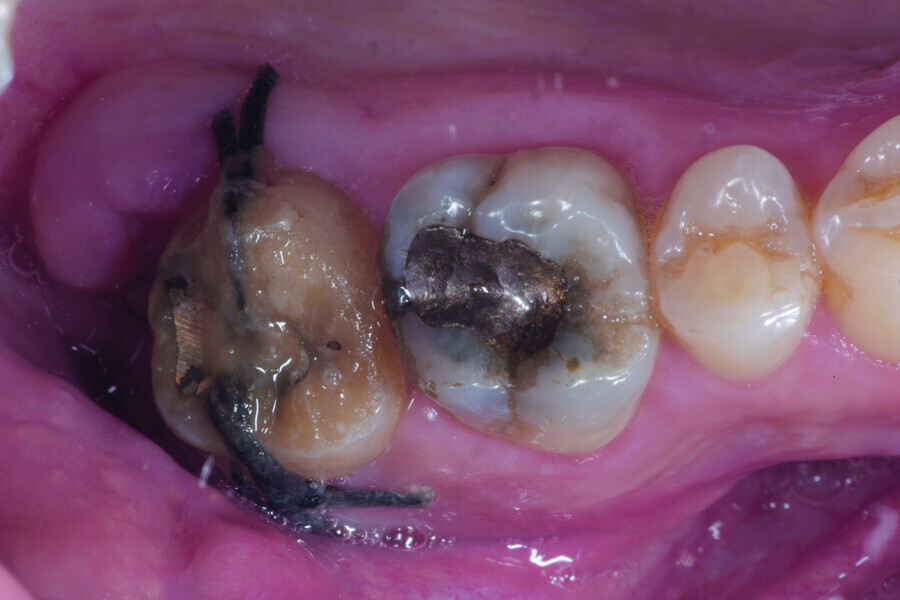

Fig. 12: Pulp chamber floor perforation, immediately after extraction.